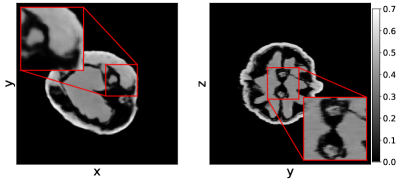

In Figure 7 we show the average and standard deviation of the TSE and the SSIM for the considered cases. We observe that U-net and MSD achieve the most accurate results and that NN-FDK and SIRT+ closely follow. The FDK algorithm is lowest in all categories. Between NN-FDK and SIRT+ we see that NN-FDK performs best for the noisy reconstruction problems and SIRT+ achieves better results for the reconstruction problems without noise. We visualize the noise for the lowest and highest in Figure 8 by showing a line profile through the center of the slice. Here we see that for the noisiest problems the amplitude of the noise can be as high as the maximum value of the phantom. In Figure 9 we show 2D slices of reconstructions of the test phantoms for the three types of reconstruction problems. In all cases we still observe reconstruction artifacts, but comparing these to the baseline FDK reconstructions, the majority is removed or suppressed.

Comparing the results to the simulated data experiments we see that SIRT+ performs worse on the experimental data, even with the additional regularization of early stopping. This is most likely due to the high-dose datasets still containing noise, whereas this is completely absent in the simulated data experiments. These differences are illustrated in Figure 10 where 2D slices of the reconstructions for the high-dose reconstruction problem with projection angles are shown.